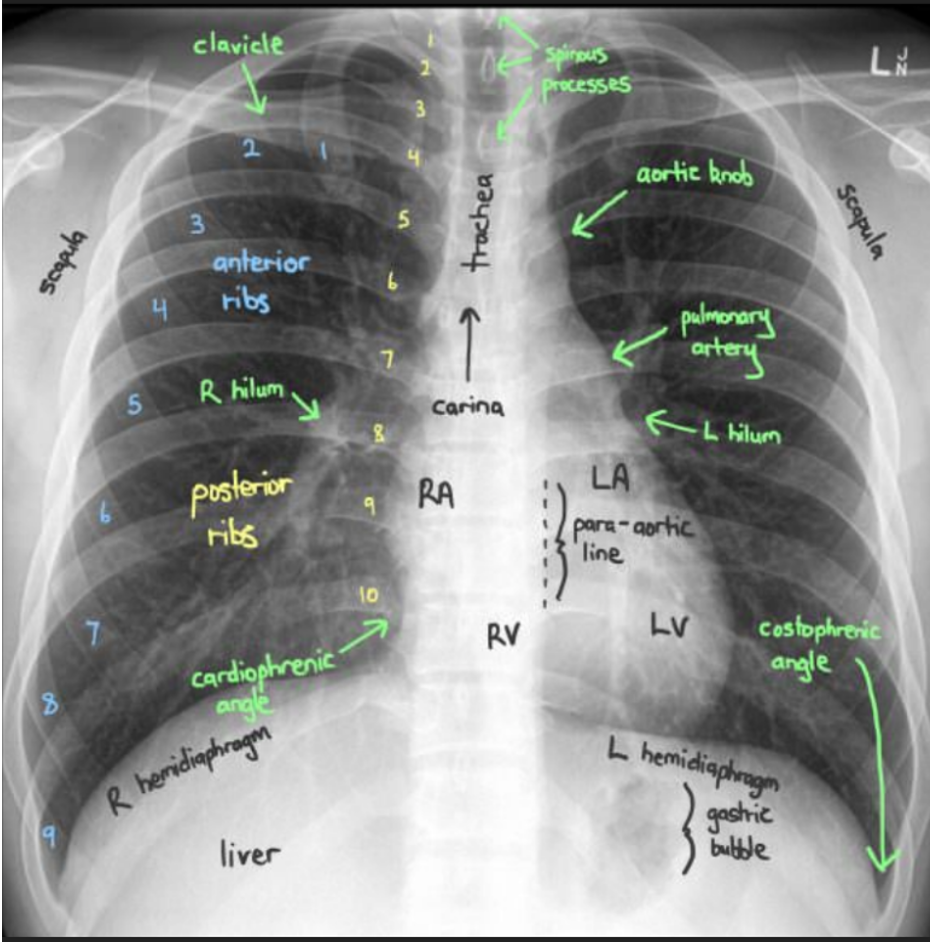

ABCDE approach to CXRAY

Airway

Breathing

Circulation

Diaphragm

Everything else

tracheal central?

• Lung fields (opacification)

• Upper

• Middle

• Lower

• Costophrenic angles

• Compare left lung to right lung

• Aortic knuckles

• L and right hilar region

• Heart size

• Cardiothoracic ratio

• Cardio phrenic angle

compare both sides

• Tented?

• Flattened?

• Pneumoperitoneum?

• Gas in stomach normal